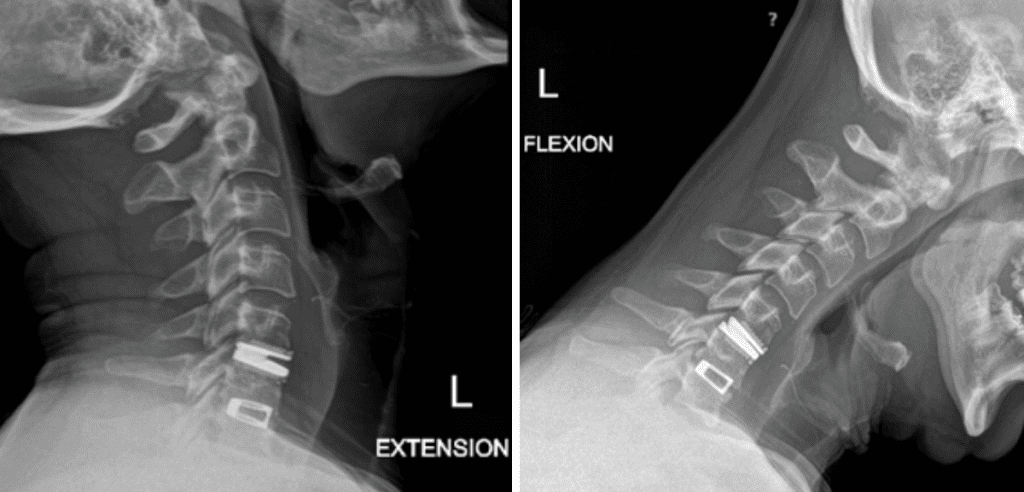

Back:

Revision Surgery Treats Intractable Neck Pain & Cervical Deformity

Author: Benjamin R. Cohen M.D., F.A.A.N.S., F.A.C.S., Read More!